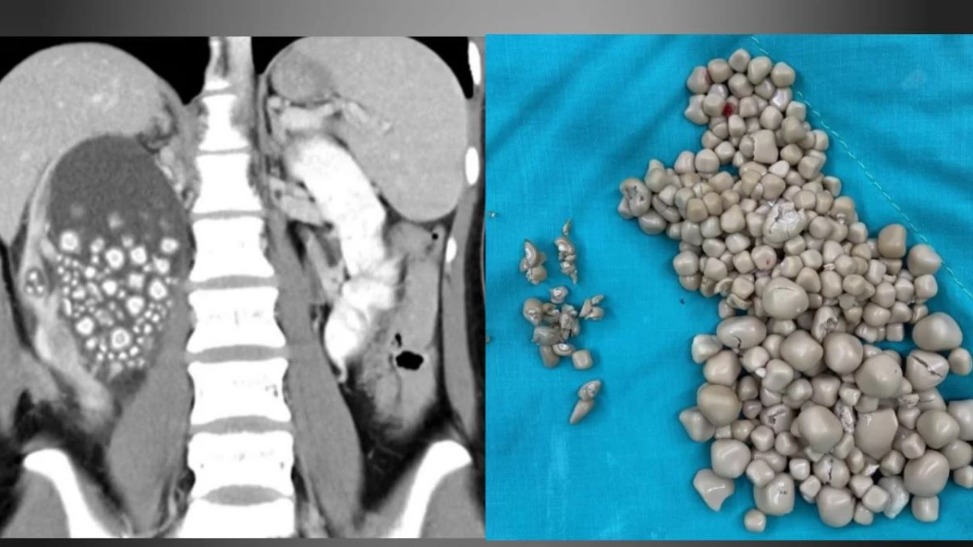

Falta de consumo de água e preferência por bebidas açucaradas levam a condição rara e grave